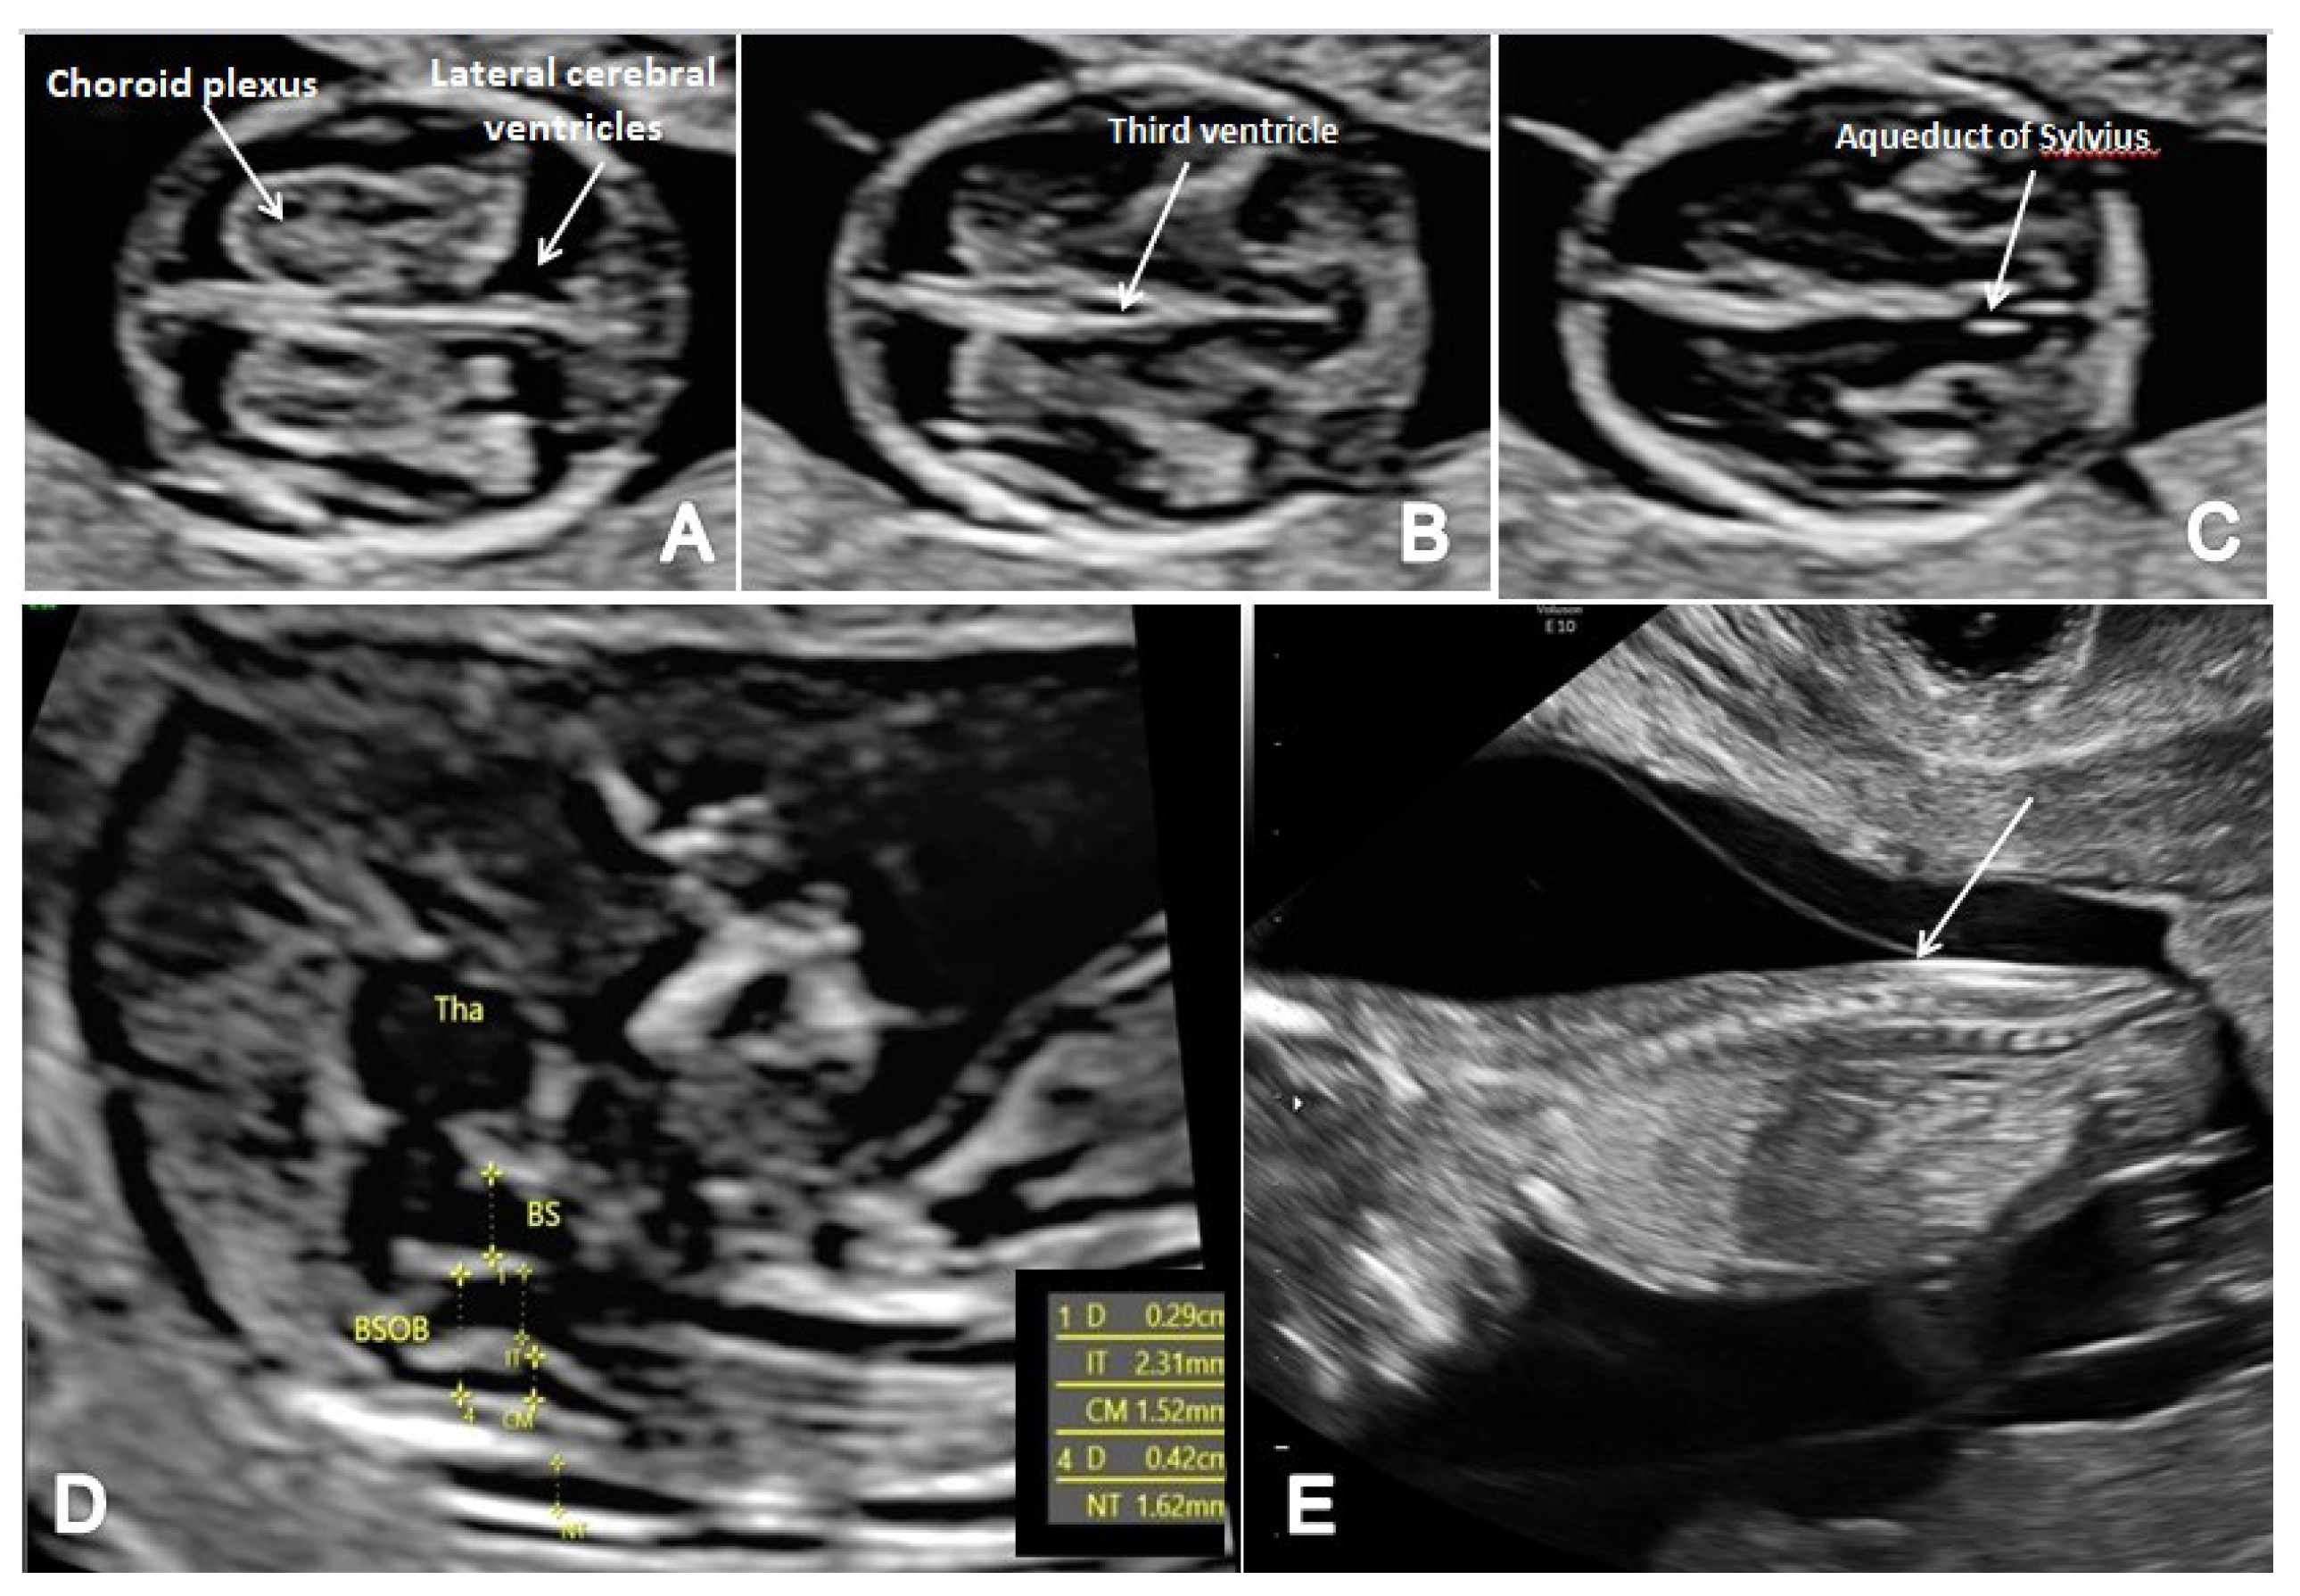

In terms of FTAS, we adopted a standard protocol that added the guidelines for basic FT screening [8] and several features for a more detailed structural assessment at this gestational age. The detailed scanning protocol included two axial planes of the brain (at the level of the choroid plexus and third ventricle and the level of the cerebral peduncles and aqueduct of Sylvius) and the sagittal view of the fetal face for the evaluation of the posterior brain complex. The scanning protocol aimed to assess the contour and shape of the fetal skull, the choroid plexus shape and relative filling of the ventricles and the aspect of the lateral cerebral ventricles (Figure 1A). We noted the presence of the third ventricle (Figure 1B) and the aspect and position of AS (Figure 1C), the presence of the CM and the fourth ventricle (the anechogenic area between the posterior border of the brain stem (BS) anteriorly and the choroid plexus of the fourth ventricle posteriorly) (IT) [13]. We investigated the presence of posterior and caudal displacement of the mesencephalon by searching for the ‘crash’ sign in the thalamic axial plane [14]. The BS/BSOB ratio was subjectively evaluated and measured when it appeared abnormal [15], and the presence of CM was noted (Figure 1D). Fronto-maxillary angle was measured in all cases, as part of the genetic screening, but narrow-angle cases were suspected also for neural tube defects [16]. In all cases, the spine was also evaluated in two-dimensional (2D) longitudinal planes, recording its regularity and the continuity of the underlying skin layer (Figure 1E).

Figure 1.

The FTAS protocol for CNS evaluation: (A) transverse view of the brain showing the contour and shape of the fetal skull, choroid plexus (arrow) and the filling of lateral cerebral ventricles (arrow); (B,C) further evaluation of the cerebral ventricular system, in transverse planes of the brain showing the third ventricle (B) and aqueduct of Sylvius (C) (arrow); (D) mid-sagittal view of the brain showing the thalamus (Tha) and the measurements for the brain stem (BS), the fourth ventricle (IT), cisterna magna (CM), the nuchal translucency (NT) and the brain stem–occipital bone ratio (BSOB); (E) longitudinal view of the spine regularity and underlying skin (arrow).